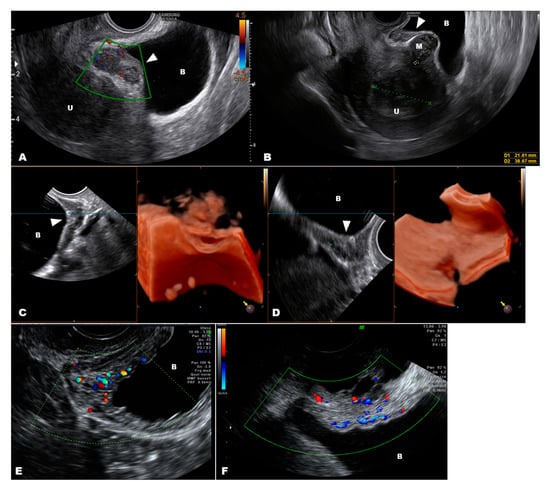

3.1. Internal Genitalia